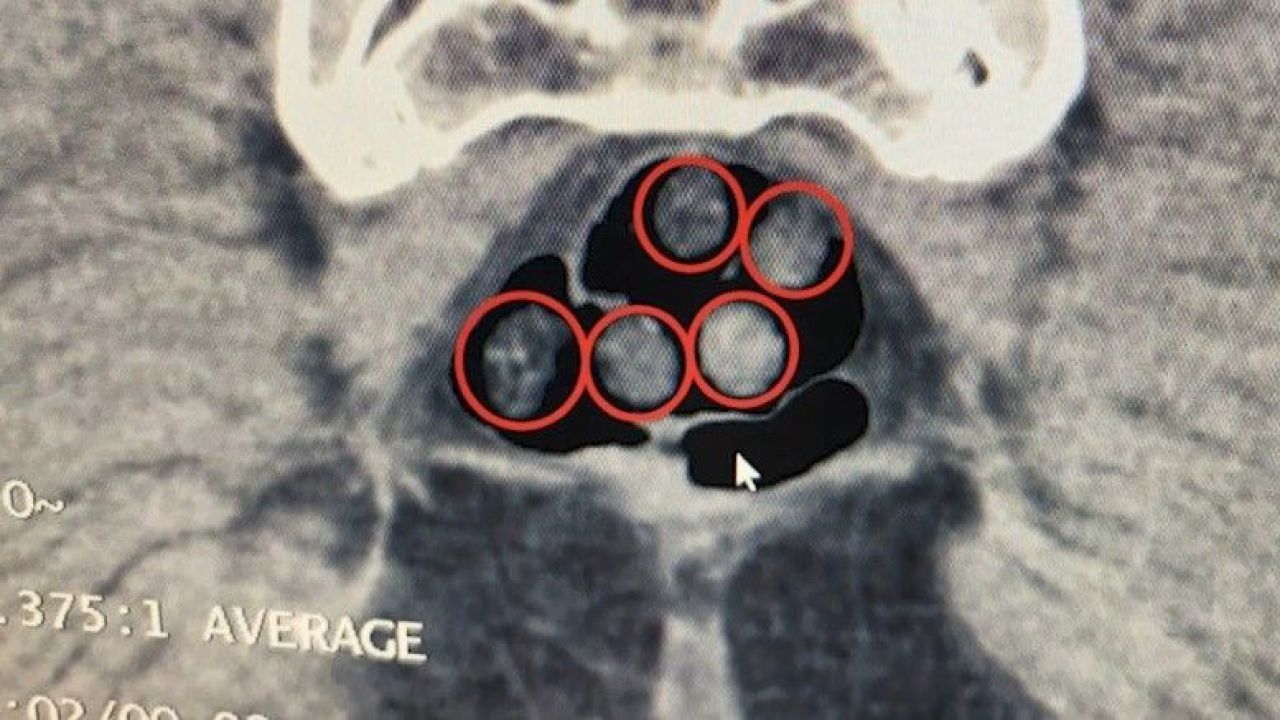

Açıklamada, “Tatvan’da durdurulan çekici üzerindeki araçta yapılan aramada 734 gram metamfetamin maddesi ele geçirildi. Olayla ilgili 2 şahıs gözaltına alındı. Yine Tatvan’da durdurulan bir otobüste yolcu olarak seyahat eden yabancı uyruklu 2 şahıs gözaltına alındı. Tatvan Devlet Hastanesinde yapılan röntgen ve tomografi incelemelerinde, şahısların mide ve bağırsaklarında çok sayıda yabancı cisim tespit edildi.

Yapılan tıbbi müdahale ile şahısların yuttuğu 14 kapsül ve üzerlerinden 36 kapsül olmak üzere toplam 50 kapsül, 385 gram metamfetamin maddesi ele geçirildi. Her iki olayda da uyuşturucu madde imal ve ticareti suçundan gözaltına alınan 4 şahıstan 3’ü çıkarıldığı adli mercilerce tutuklandı. Hemşehrilerimizin huzuru ve güvenliği için uyuşturucu madde imalatı, kaçakçılığı ve kullanımına karşı yürütülen kararlı mücadelemiz devam edecektir.” denildi.